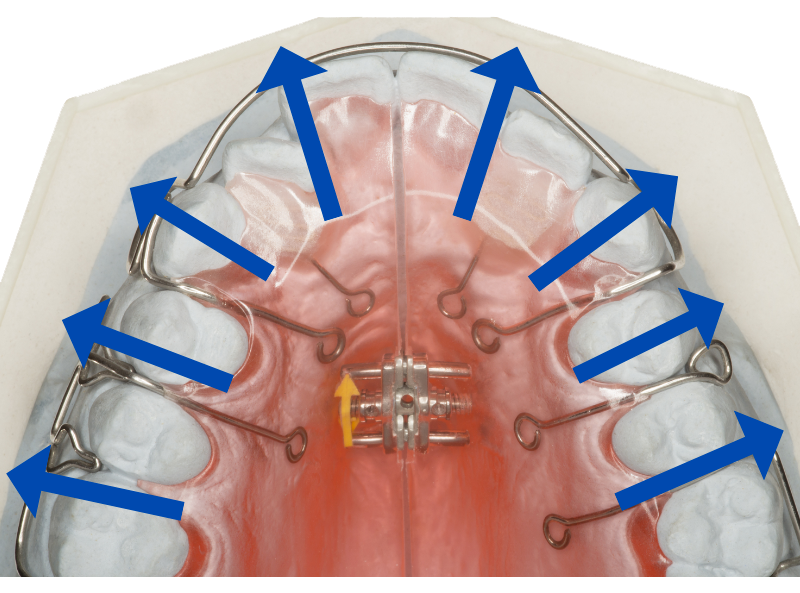

先ほどご説明した通り、小顔で顎が小さい方はスペースが足りません。そこでスペースを確保するために、前歯しか動かせない格安矯正でよく用いられるのが、拡大床という治療法です。

拡大床

ネジの力を利用して歯を外側へ押し広げることで、前歯を並べるスペースを確保します。

ただ拡大床は、歯列を広げすぎないよう細心の注意を払う必要がある、とても難しい治療法

経験不足の歯科医師では、過度に歯を押し広げてしまい、口ゴボかえって酷くなることがあります。

またこの拡大床は奥歯を左右に広げようとしますから、経験不足の歯科医師では、奥歯の位置がおかしくなってしまうことも。

そのため噛み合わせが悪くなって、食事に支障をきたす、という失敗症例もよく耳にします。

上記のような失敗を起こさないために当院では、奥歯奥側移動してスペースを確保できるマウスピース矯正「インビザライン」をおすすめしています。

その点インビザラインでは、親知らずを抜いたスペースに一番奥の歯を動かします。

それにより空いたスペースに次の奥歯を動かし、さらに次の奥歯を動かします。

こうして順繰りに奥へと歯を移動させることで、4〜5mm以上のスペースを確保して、前歯をきれいに並べられるのがインビザラインの優れたポイント。

この方法なら親知らずを抜いた広いスペースを利用できますから、あごが小さくて口ゴボでお悩みの患者さまでも治療可能です。

またインビザラインは、奥歯の傾きをまっすぐにするだけでなく、奥歯を奥側に移動することもできます。

その点インビザラインでは、親知らずを抜いたスペースに奥歯を移動させることで、前歯をきれいに並べるスペースを確保できます。

インビザラインでは、親知らずを抜いたスペースに一番奥の歯を動かします。

こうして順繰りに奥へと歯を移動させることで、前歯引っ込めるスペースを確保できるというのがインビザラインの優れたポイント。

この方法なら親知らずを抜いた広いスペースを利用できますから、小顔であごが小さい患者さんでも、前歯引っ込める矯正が可能なのです。

なお奥歯を奥側へ動かすこの治療法は「インビザライン」でしか行えません。格安矯正はもちろん、ワイヤー矯正でもできないのでご注意ください。